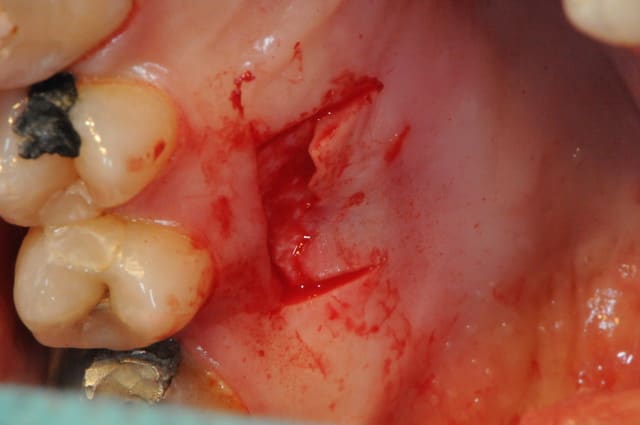

Le cas EII sur 12

positionnement de l'implant en ménageant un espace en vestibulaire qui st comblé avec de l'os synthétique car l'espace est important et il y a une perforation de la corticale vestibulaire en regard de l'apex de la dent.

pour recouvrir tout cela et gagner un peu de volume vestibulaire

un lambeau palatin pédiculé qui après une rotation va recouvrir l'implant et la greffe.